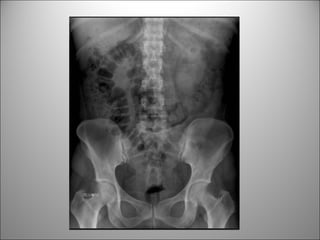

PROYECCIÓN ESTÁNDAR

• DECÚBITO SUPINO

PATRÓN DE GAS INTESTINAL

• Contraste natural

• Puedo diferenciar entre Int. delgado y cólon?